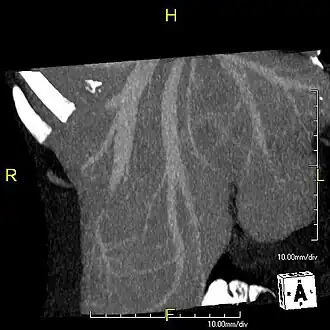

Left lobe liver tumor

The liver is a vital organ and supports almost every other organ in the body. Because of its strategic location and multidimensional functions, the liver is prone to many diseases.[58] The bare area of the liver is a site that is vulnerable to the passing of infection from the abdominal cavity to the thoracic cavity. Liver diseases may be diagnosed by liver function tests–blood tests that can identify various markers. For example, acute-phase reactants are produced by the liver in response to injury or inflammation.